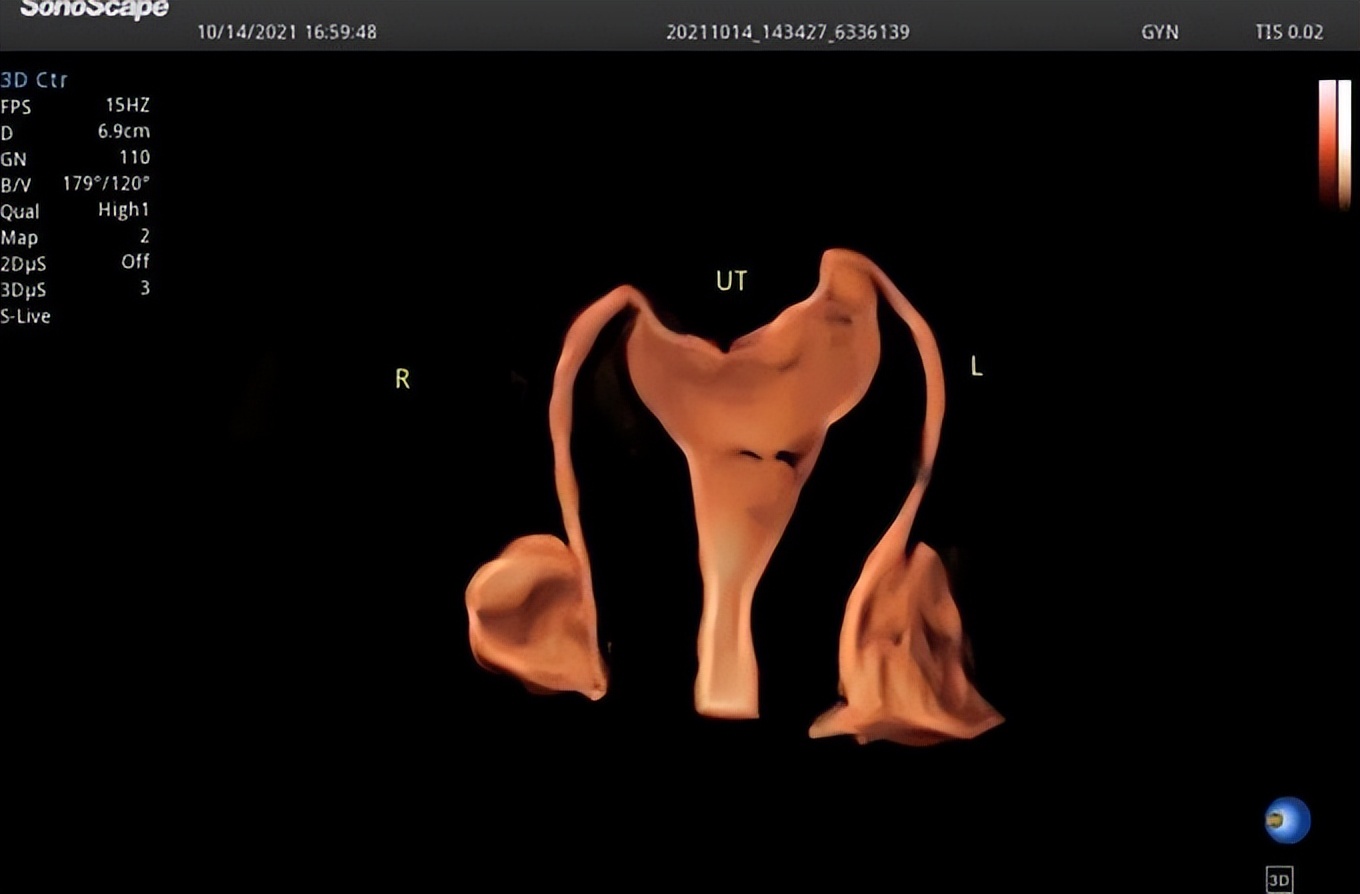

子宫输卵管造影是指在宫腔插管下向宫腔内注入超声微泡,通过四维超声,实时显示宫腔的形态、输卵管的走形以及盆腔的弥散情况, 从而来评估双侧输卵管的通畅性,可同时观察子宫、输卵管和卵巢等是否存在病变 。

4、宫腔、输卵管显影快捷,图像清晰,实时动态,更加立体准确地反映子宫输卵管的结构、 走形以及阻塞部位,获得更多临床需要的信息;